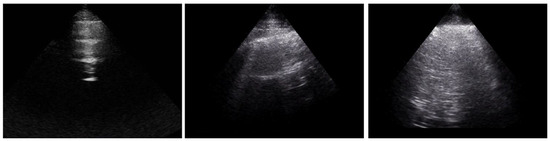

The B-lines were separately quantified with LUS by two assessors (LG, GL), who examined 21 intercostal spaces from the posterior (13 spaces) and anterior (8 spaces) chest wall. Examples of the assessment of LUS space are presented in Figure 1. The sum of anterior and posterior B-lines determined the total B-lines number.

Figure 1. Example of normal LUS (left panel), LUS with 1 B-line (central panel) and with multiple B-lines (right panel).